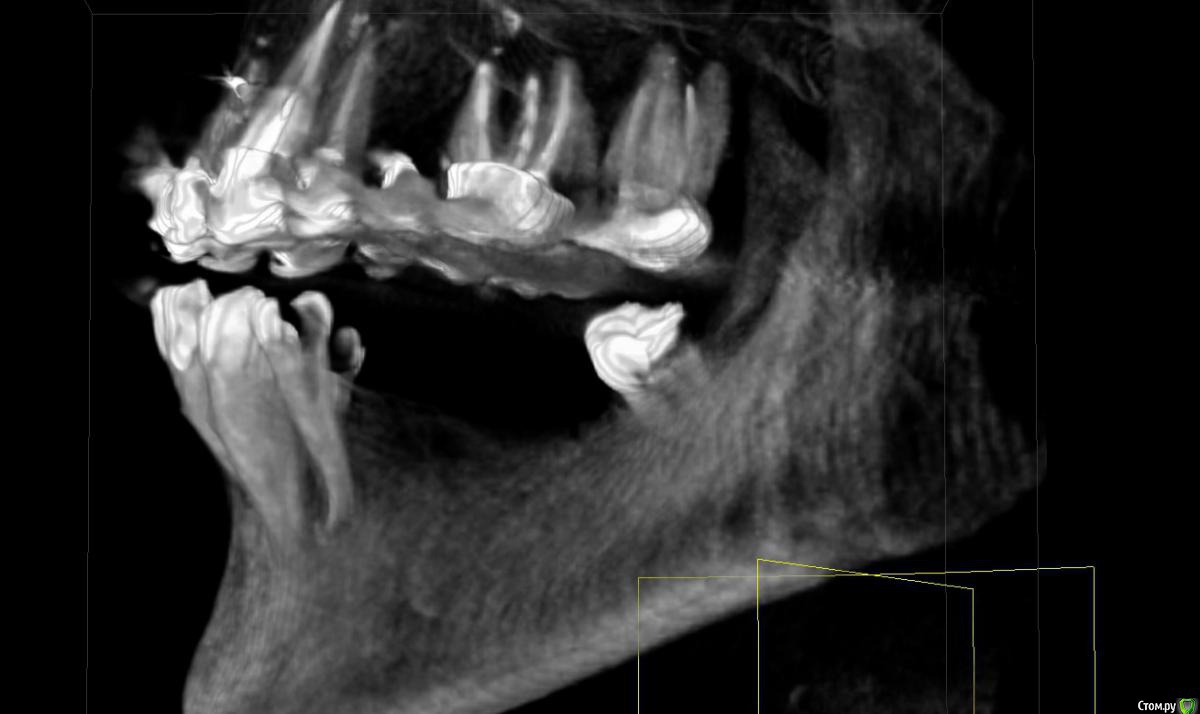

Прошу совета по плану остеопластики с дальнейшей имплантацией (на нижней челюсти).

53 года. Необходимо протезирование нижней челюсти.

Все врачи говорят о недостатке костной ткани (3мм).

Все говорят о необходимости удалить 4-ку слева (так как большая киста, зуб спасти невозможно). Вопросы по поводу дальнейших действий и общей стратегии протезирования.

Снимки месячной давности (8-ка уже удалена). Прикус на этом снимке не видно, нижняя челюсть смещена внутрь по отношению к верхней (не знаю, важно ли это)

я попыталась сделать принтскрины с 3D, но, к сожалению, не очень понимаю, какие снимки (углы, ракурсы) нужны, может быть сделала не то и не так, сорри. Понимаю, что скачивать 3D времени у большинства нет.

post-48869-0-20530400-1472582105_thumb.jpg

post-48869-0-99232900-1472582231_thumb.jpg

post-48869-0-09101500-1472582237_thumb.jpg